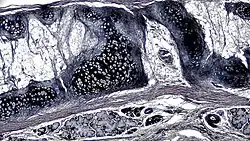

![]() A cross section of mammalian elastic cartilage | |

Elastic cartilage is histologically similar to hyaline cartilage but contains many yellow elastic fibers lying in a solid matrix. These fibers form bundles that appear dark under a microscope. The elastic fibers require special staining since when it is stained using haematoxylin and eosin (H&E) stain it appears the same as hyaline cartilage.[3] Verhoeff van Geison stains are used (giving the elastic fibers a black color), but aldehyde fuchsin stains, Weigert's elastic stains, and orcein stains also work.[3] These fibers give elastic cartilage great flexibility so that it is able to withstand repeated bending. Similarly to hyaline one or multiple chondrocytes lie between the spaces (or lacunea) in the fibres.[2] the chondrocytes only make up 2% of the tissue's volume.[2] chondrocytes and the extracellular matrix are contained in an outerlayer named the perichondrium[2] (which is a layer of dense irregular connective tissue that surrounds cartilage which is independent of the joint).[3] It is found in the epiglottis (part of the larynx), and the pinnae (the external ear flaps of many mammals). Elastin fibers stain dark purple/black with Verhoeff's stain.